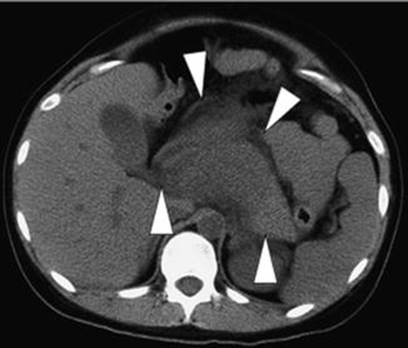

Computed tomography (CT) should be avoided, especially during the first trimester, because of radiation exposure to the fetus, but has to be performed when benefits outweighed the risk. Imaging diagnostic modalities are used not only for the diagnosis but also to provide information about the severity in AP (Figs. 3.8, 3.9, 3.10, and 3.11) [290]. In a series of 12 cases of AP in pregnant women with AFLP, Moldenhauser et al. [110] found that imaging techniques (ultrasound and computed tomography) were accurate in only 58 %. In addition, if thyroid ultrasound is equivocal, a helical CT scan is helpful in mediastinal parathyroid adenoma localization, especially during pregnancy when radioisotope techniques are contraindicated.

Fig. 3.8

Computed tomogram on admission of a 25-year-old primigravida at 35 weeks of gestation shows marked swelling of the pancreas (arrowheads) and effusion around the pancreas [289]